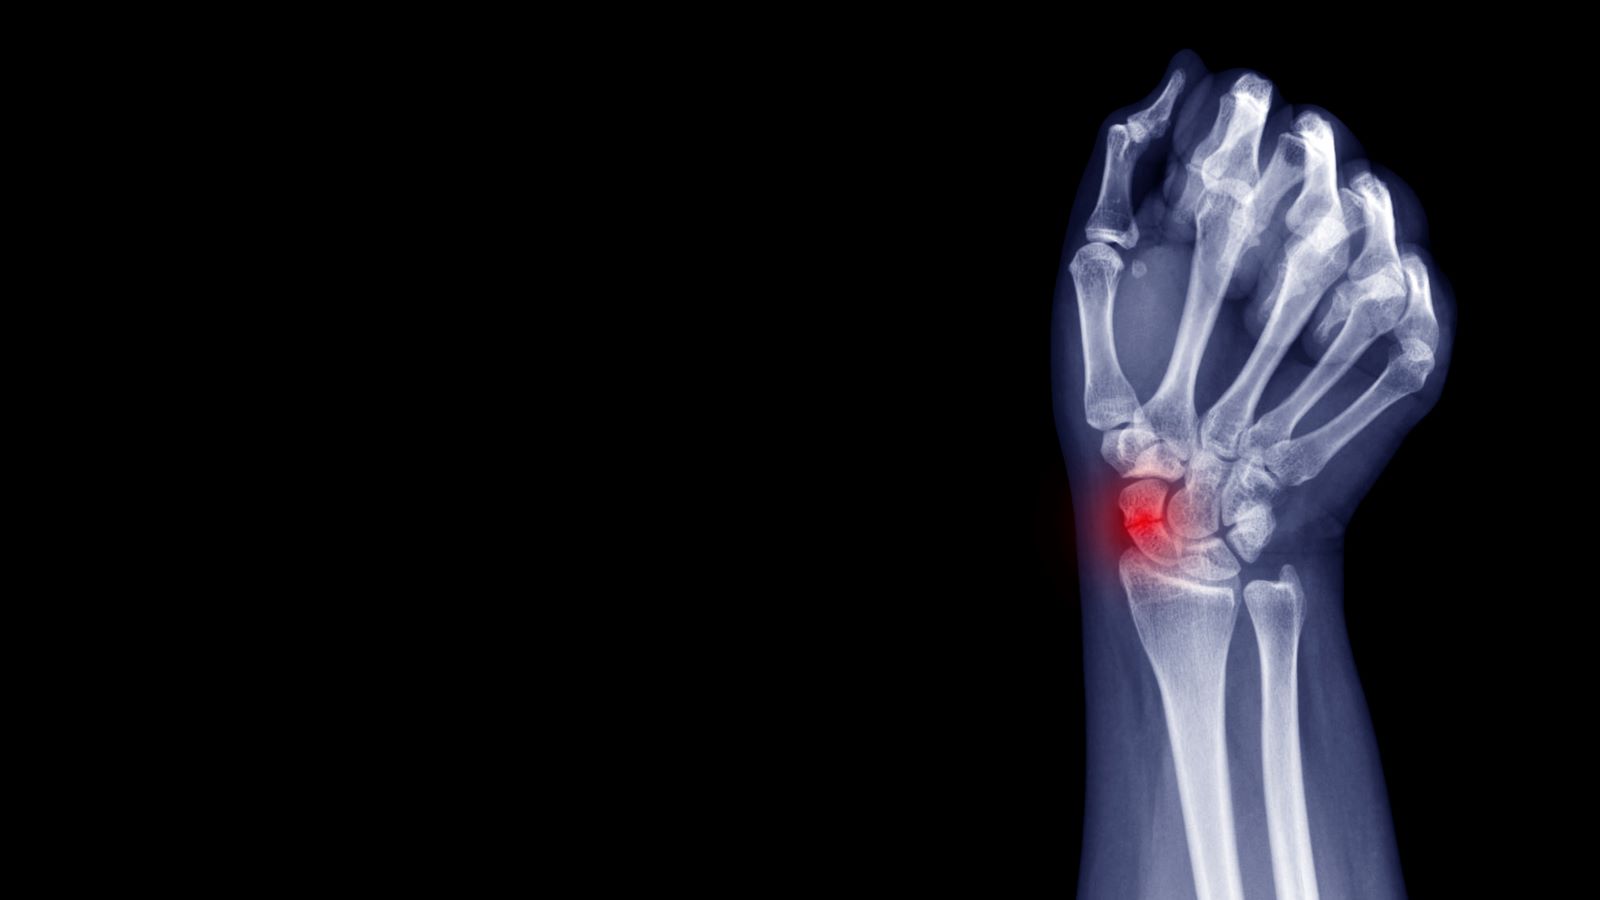

Scaphoid Fracture No Swelling . When a scaphoid fracture occurs, it interferes with a person’s ability to move their wrist joint. What is a scaphoid fracture, and how does it happen? Prompt treatment can help prevent complications and promote correct healing. Here are some scaphoid fracture causes and symptoms to help you get. Most people with a scaphoid fracture (which is the same as a broken wrist) will have pain and/or swelling along the thumb side of the wrist within days following. Scaphoid fracture is a break in the scaphoid bone, one of the small bones in your wrist. Breaks are often caused during falls or as a result of repeated use of the wrist in. Symptoms of a scaphoid fracture typically include swelling and pain in the wrist just below the base of the thumb. Scaphoid fractures are the most common carpal bone fracture, often occurring after a fall onto an outstretched hand.